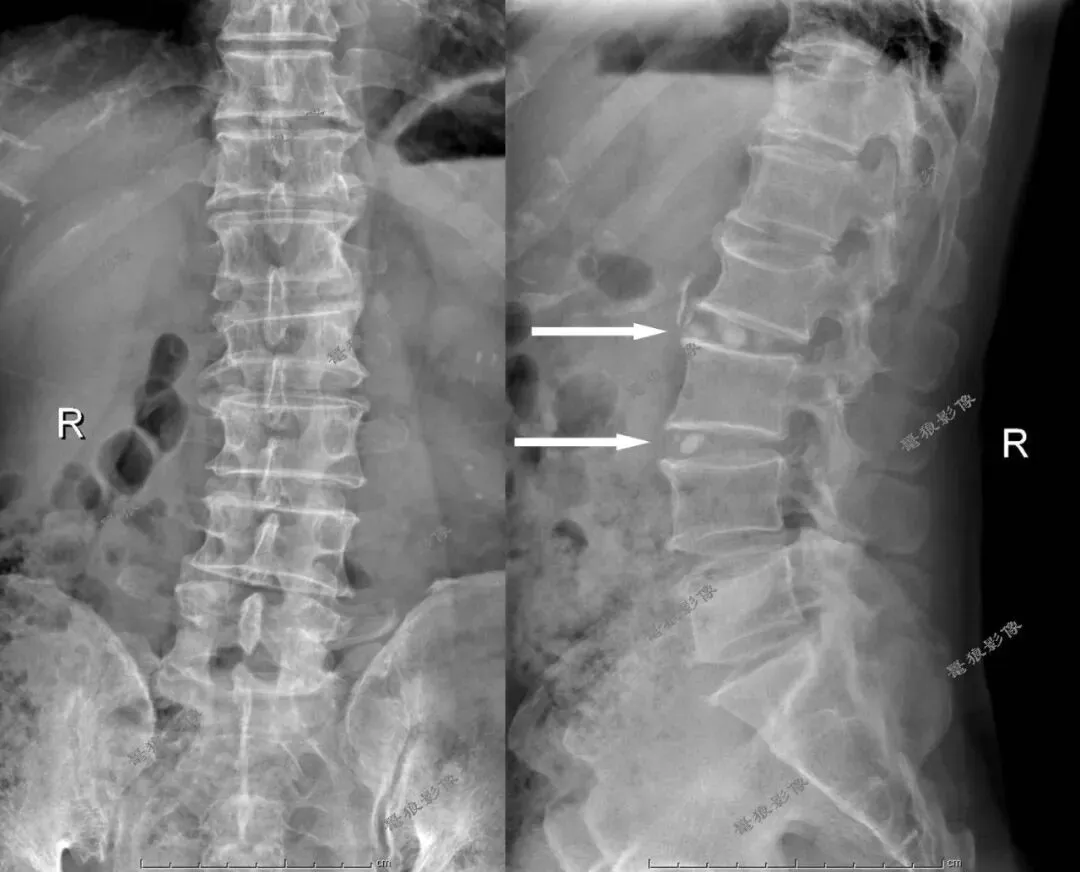

M,60y。腰部及左髋疼痛1月。

一、行腰椎+骨盆X线平片提示:

1、腰椎退行性改变;腰2/3、腰3/4椎间隙多个小圆形高密度影,性质未明,建议进一步检查。

2、骨盆退行性改变。

3、左下腹见斑片状高密度影,建议进一步检查。